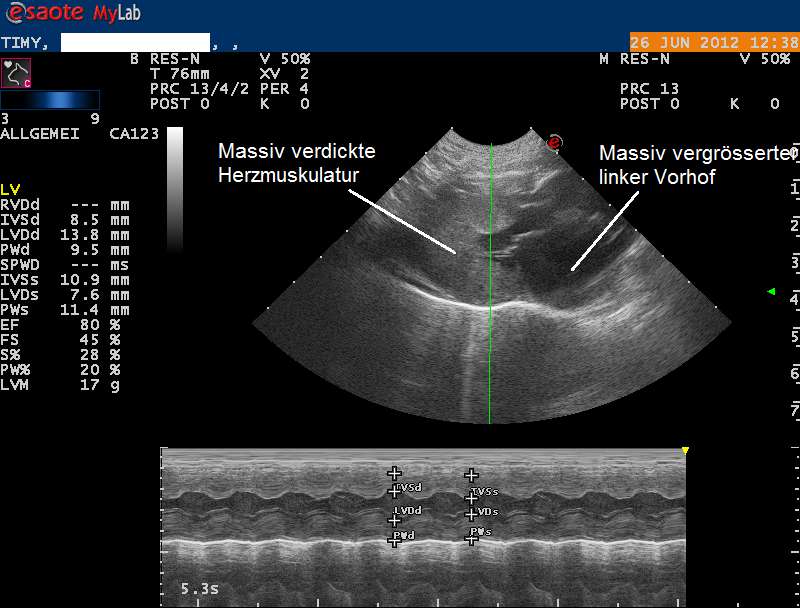

Die Röntgenbilder weisen auf eine Herzerkrankung hin, welche zum Verschluss der Körperschlagader geführt haben könnte. Das Herz wird mittels Ultraschall genauer untersucht, und es zeigt sich, dass die Muskulatur der Herzkammern sehr stark verdickt und die Vorhöfe stark erweitert sind. Eine Diagnose einer Hypertrophen Kardiomyopathie (HCM) wird gestellt.